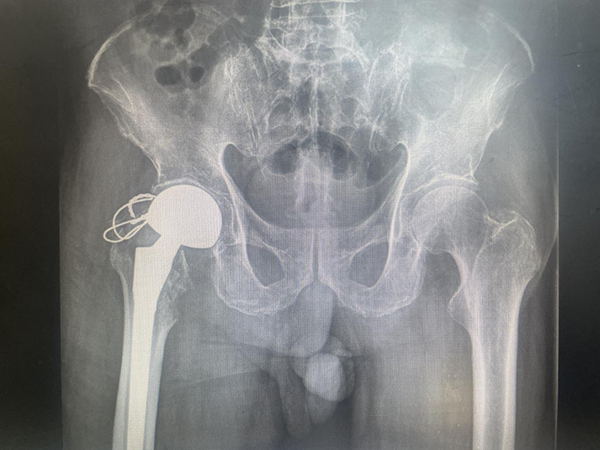

89歲的陳大爺在家中不慎摔倒,右側(cè)髖部著地后無(wú)法站立。于當(dāng)?shù)鼐驮\行X線檢查后診斷為“髖部骨折(股骨粗隆間骨折)”。髖部骨折又被稱為“人生的最后一次骨折”。75歲以上老人如遭遇髖部骨折,生活將難以自理,大部分需要長(zhǎng)期臥床,極易導(dǎo)致褥瘡、肺炎和血栓的發(fā)生,嚴(yán)重可危及生命。因此,髖部骨折建議首選手術(shù)治療。陳大爺經(jīng)兩月保守治療無(wú)果后,為尋求站起來(lái)的可能,來(lái)到徐州市中醫(yī)院骨科就診。如何為陳大爺選擇一個(gè)合適的手術(shù)方案顯得尤為重要。89歲高齡,臥床保守治療期間出現(xiàn)肺部感染及深靜脈血栓等并發(fā)癥,既往有房顫、肺栓塞等病史,此次髖部骨折對(duì)陳大爺來(lái)說(shuō)意味著直面死亡。即便高齡,但陳大爺思維清晰,下地行走活動(dòng)欲望強(qiáng)烈,經(jīng)過(guò)溝通后堅(jiān)持要求給予手術(shù)治療。

●(術(shù)前X線片)